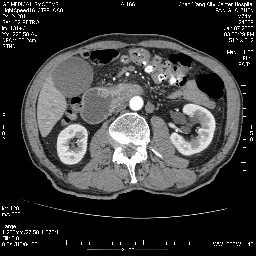

女,74岁,呕吐10余日

壶腹部的占位性病变,考虑为十二指肠癌并梗阻,但脾内多发性低密度区为转移吗?

还有胃、脾之间可见有侧支循环建立。左肾盂积水。

考虑来源于十二指肠水平段的恶性占位,侵及周围组织,特别是胰腺,可见区域淋巴结肿大,左侧下腔静脉畸形。

十二指肠水平段腔内占位伴梗阻,中等度较为均匀的强化,洗脱慢,区域淋巴结显示增多,符合腺癌表现。下腔静脉变异。

十二指肠降段扩张,水平段狭窄成鼠尾状,肠壁明显增厚,胰腺勾突增大成不均匀强化,其内可见低密度区,胆囊增大,1十二指肠水平段腺癌侵犯胰腺勾突可能大,2胰腺癌侵犯十二指肠(只有胆囊增大没有肝内外胆管扩张不好解释)代除外.

上消化道造影见十二指肠结节状充盈缺损,ct增强十二指肠壁局限性增厚并强化,考虑十二指肠壶腹癌?

十二指肠降段扩张,水平段狭窄成鼠尾状,肠壁明显增厚,胰腺勾突增大成不均匀强化,其内可见低密度区,胆囊增大,1十二指肠水平段腺癌侵犯胰腺勾突可能大,2胰腺癌侵犯十二指肠 。

今日手术结果:胰腺钩突癌侵犯十二直肠,腹腔淋巴结转移.